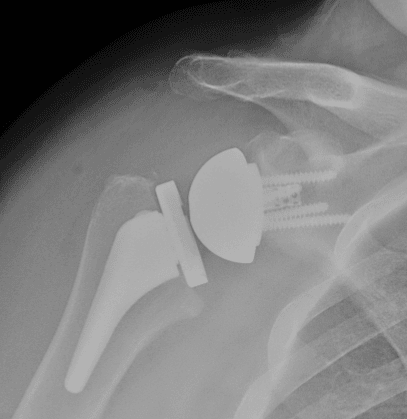

Total shoulder joint replacement

A total shoulder joint replacement.

Before and after total shoulder replacement

These X-rays were taken before and after total shoulder replacement surgery for osteoarthritis.